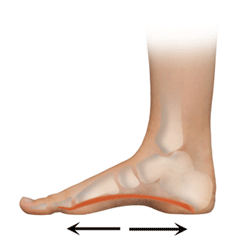

00-1010人们出现足跟痛的原因有几个,比如足底的筋膜,(即跖腱膜.的跟腱与骨连接的部位,和劳损)的炎症和劳损还有一些人与先天的足部发育,(如扁平足,)有问题,这很可能导致足跟痛。此外,体重过大,长时间负重行走和过度锻炼、过度运动的人也容易出现足跟痛,一些慢性病患者,如糖尿病患者,也是足跟痛的高危人群。